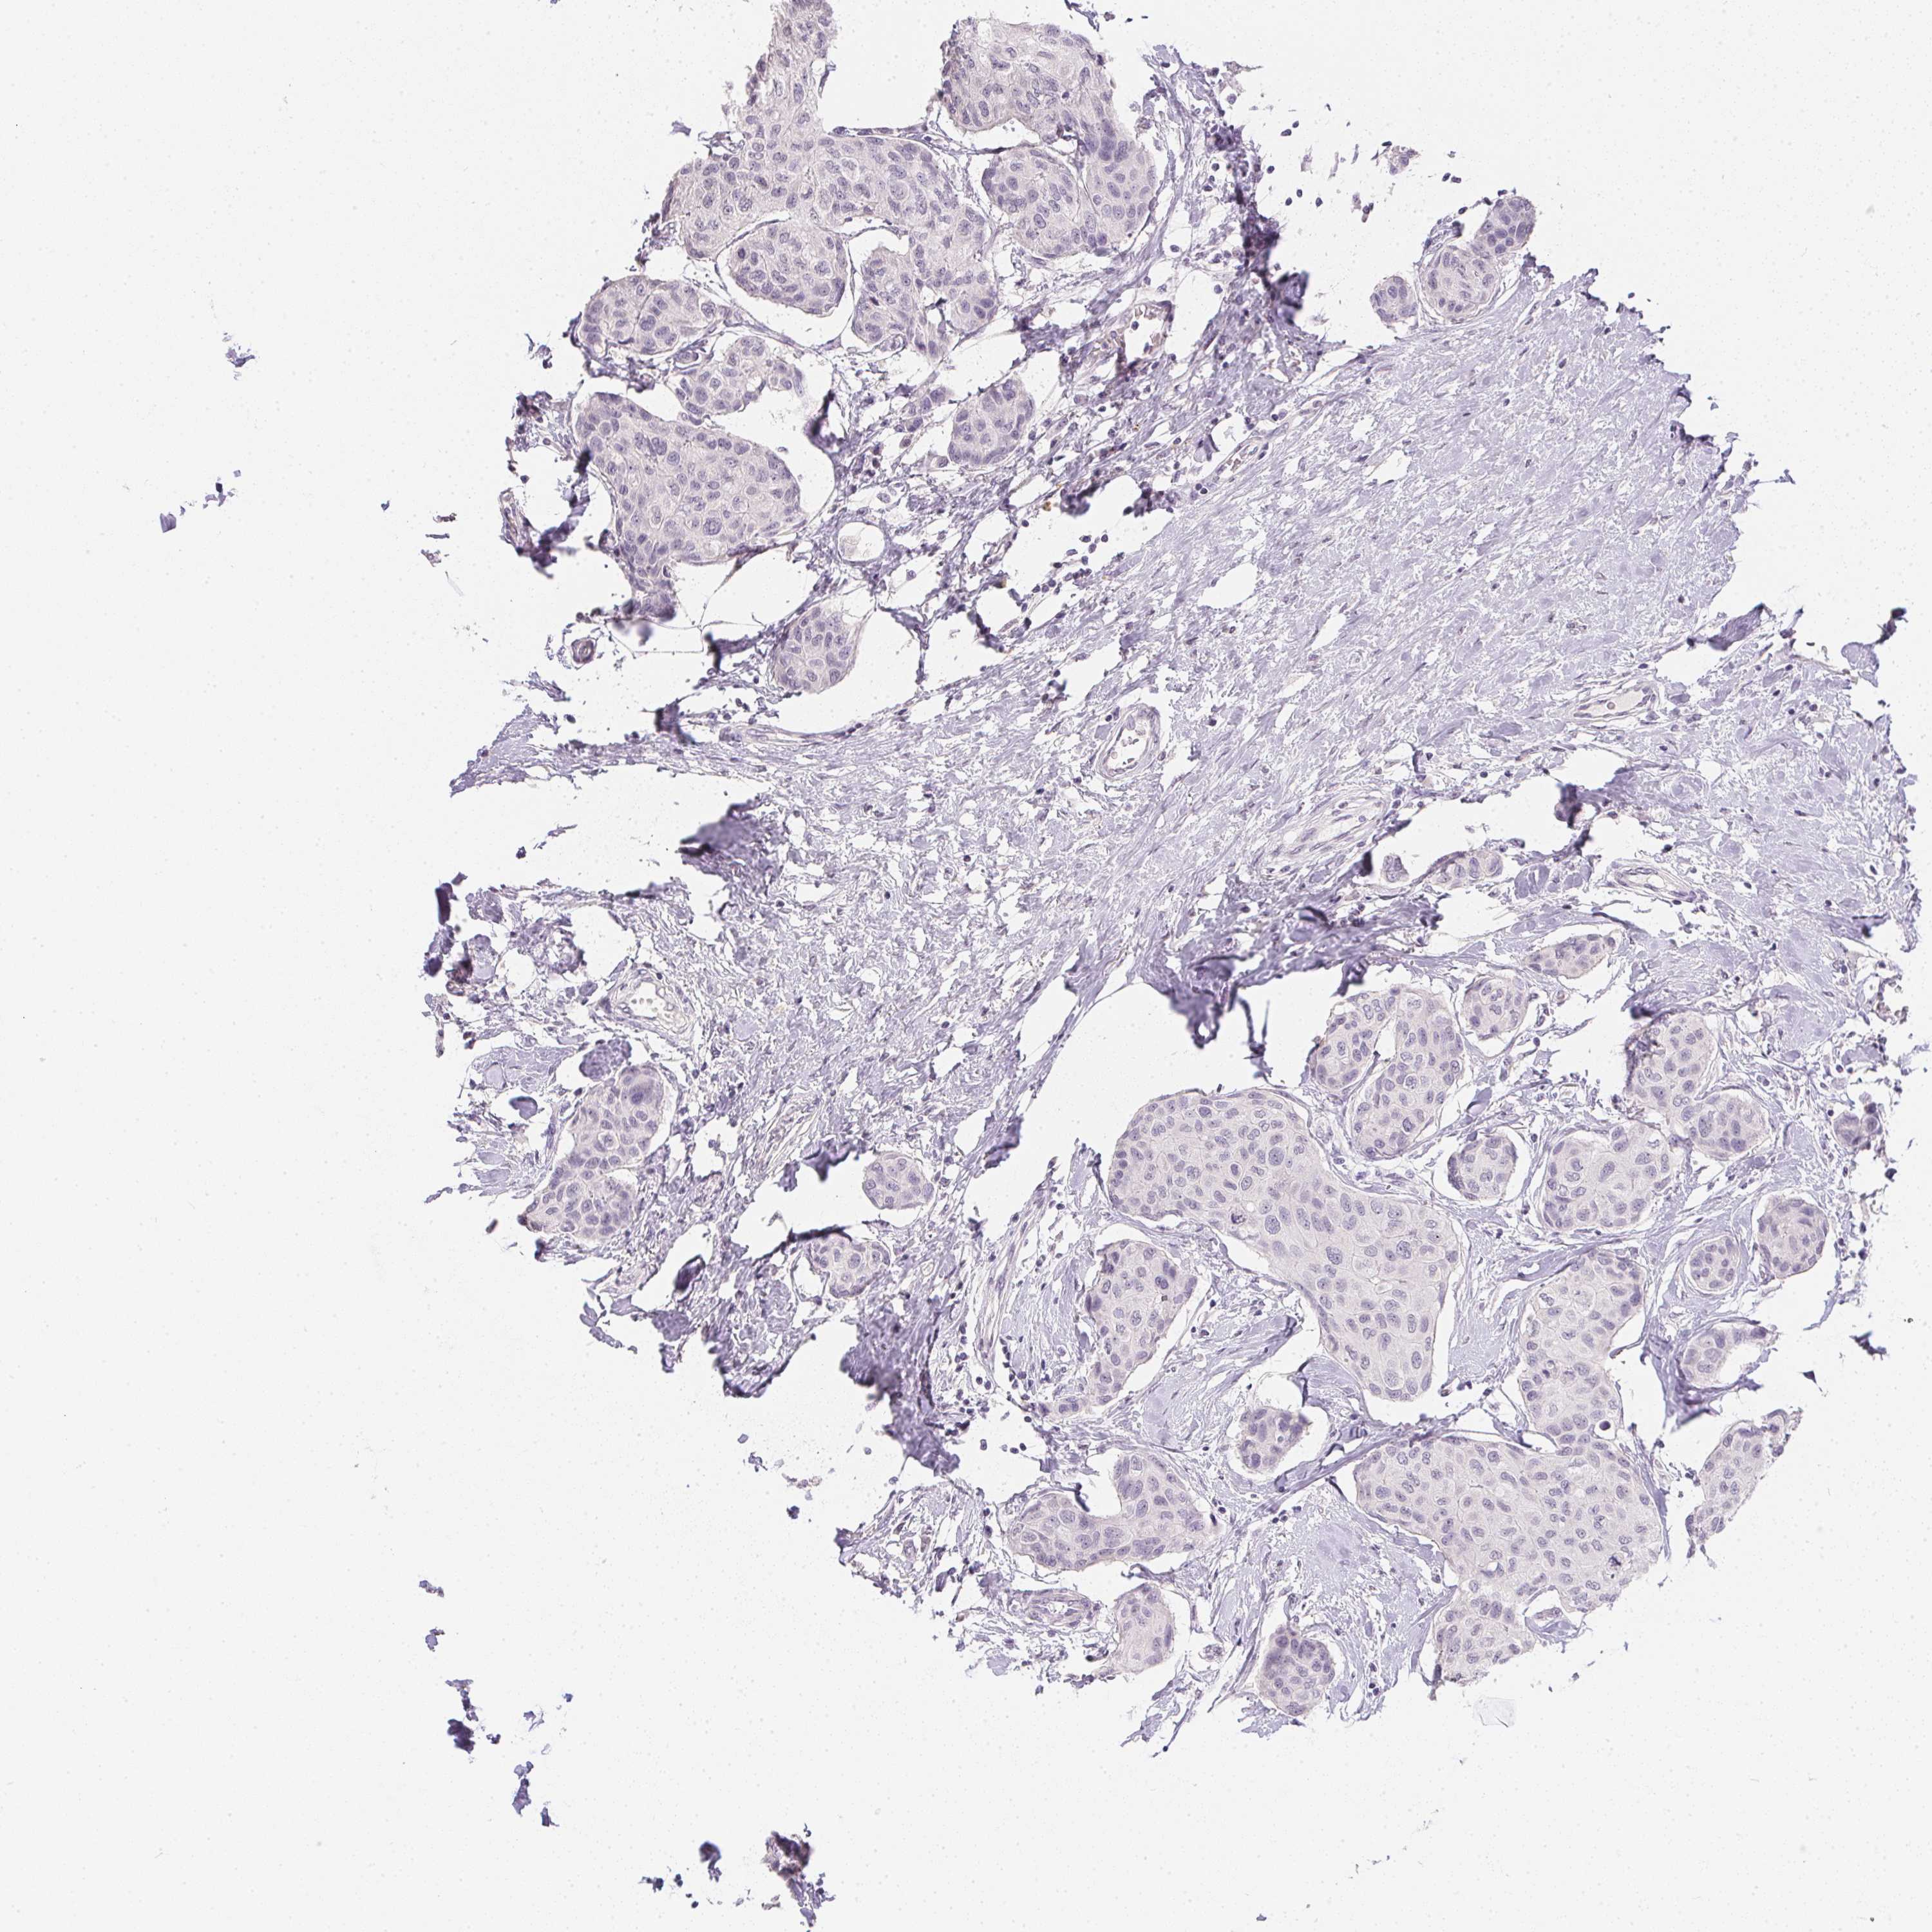

CANCER BREAST CANCER Show tissue menu

Breast cancer

Human cancer